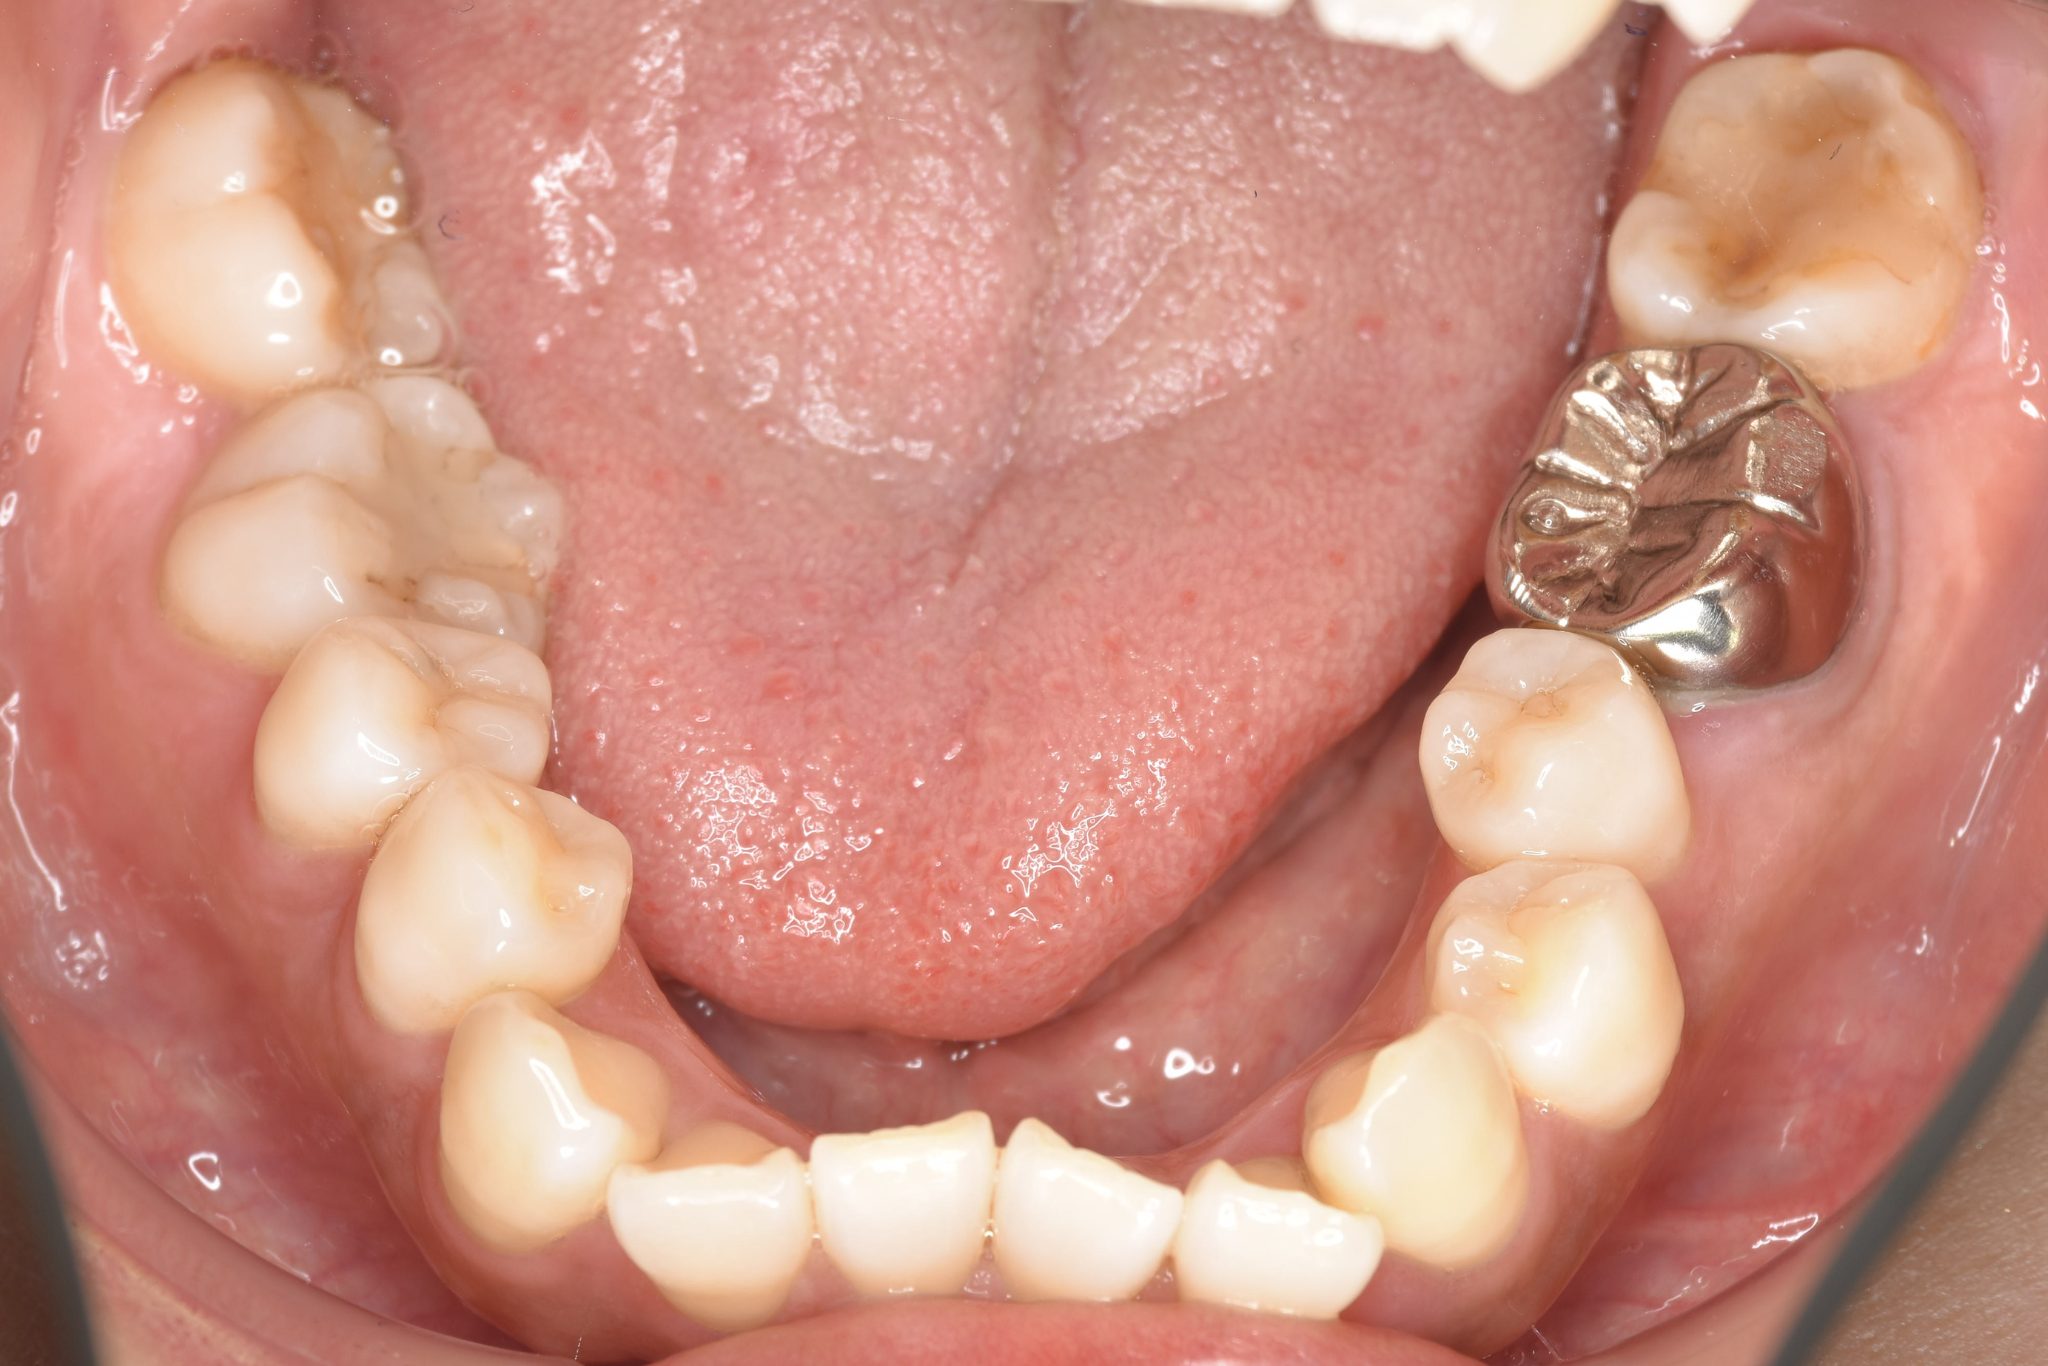

ビフォー

全顎ワイヤー矯正 症例_141